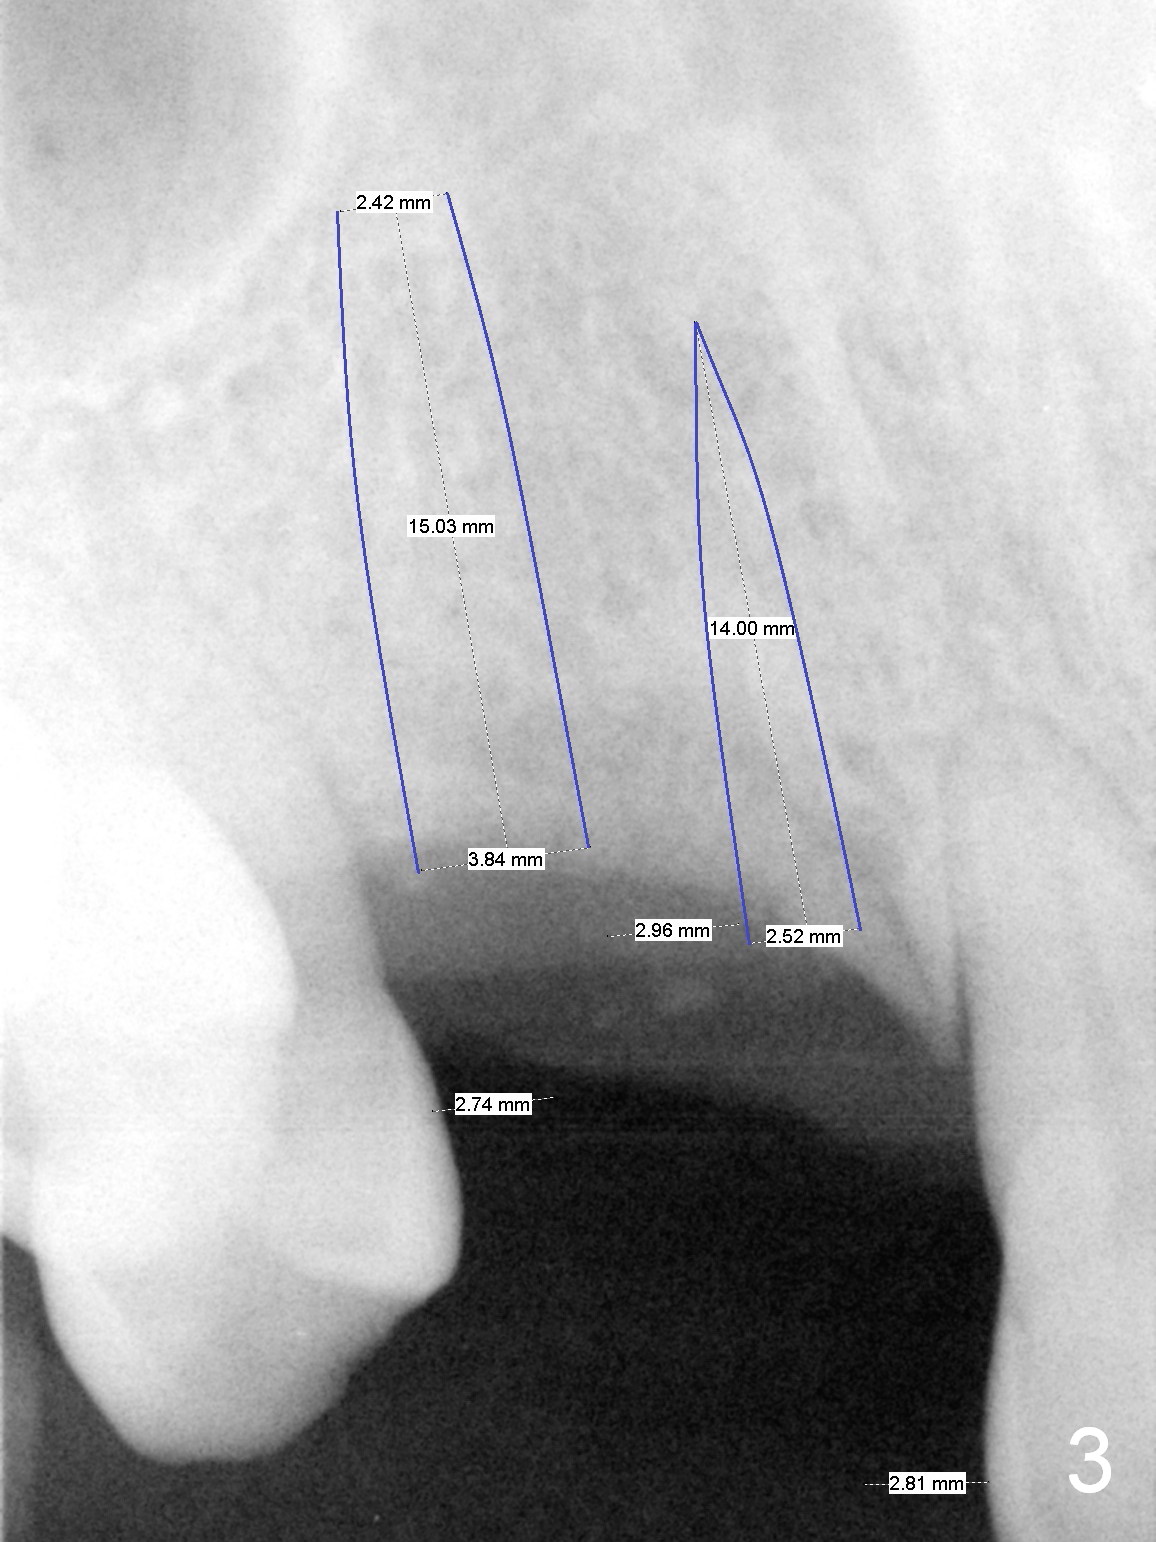

The bone height at #15 is unfavorable (Fig.4). Use 1.6 mm drill for 6 mm to start osteotomy, followed by Magic Expanders (BEB). Since the restorative height is limited due to long-standing edentulism with the supraerupted opposing tooth (Fig.5), consider using Magicore (blue). Use the bone condenser with stopper from Sinus Master kit for sinus lift. Place bone graft distally (red circles), followed by resorbable and nonresorbable collagen membranes (green curved line).